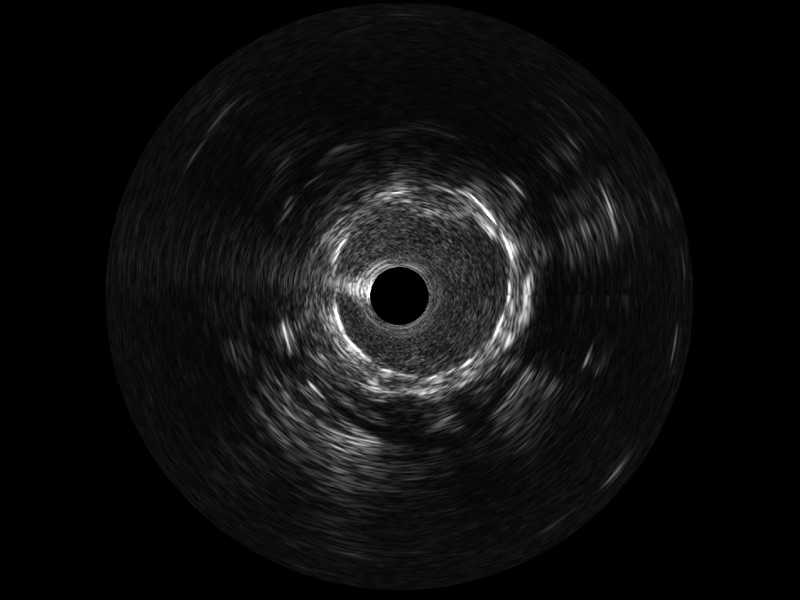

傳統(tǒng)IVUS圖像

對比傳統(tǒng)IVUS導(dǎo)管成像,開立寬頻IVUS圖像的近場支架梁顯影更細(xì)膩,遠(yuǎn)場中膜外血管仍清晰可辨,兼顧遠(yuǎn)中近,兼顧分辨力與穿透深度